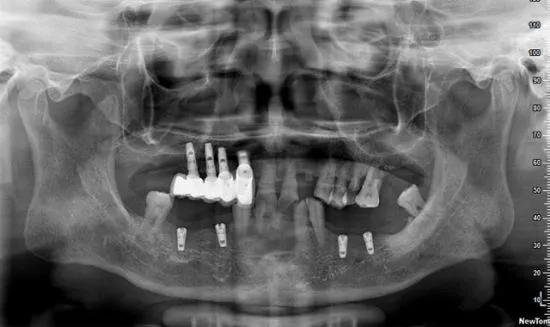

05、口腔全景片+口腔CT

检查缺牙后是否满足种植牙条件

种植牙是目前缺牙修复的最好方式

但种植牙对牙槽骨、口腔健康等有相应要求

因此缺牙拍全景片+口腔CT

可检查牙槽骨是否萎缩、口腔健康状况是否良好

利于种植前对牙槽骨的质量评价、种植体大小及长短的确定

方便医生根据实际情况,量身定制种植牙方案